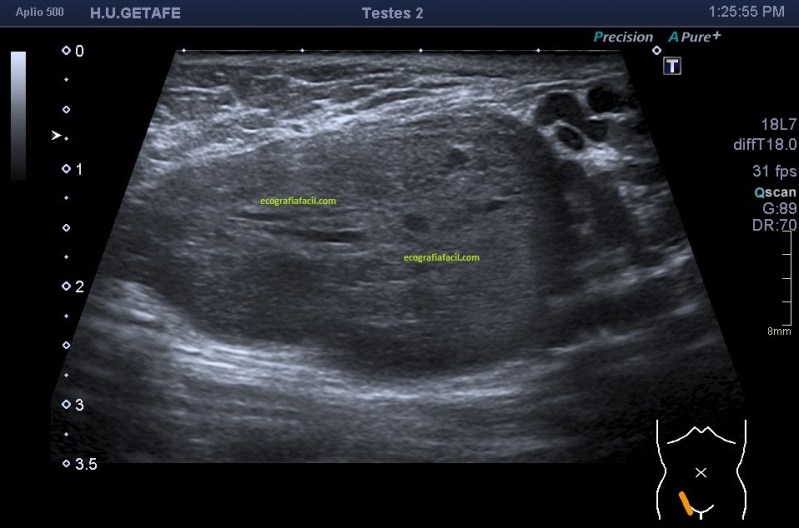

En cuanto la paciente me indicó su zona de dolor y pude el transductor observé una imagen mal definida que ocupaba la porción inferior del músculo recto abdominal derecho (coincidiendo con foco doloroso), se visualiza una lesión de ecogenicidad heterogénea (predominio hipoecogénico) con bordes irregulares de aproximadamente 2,5 cms en su eje más largo.

Semiológicamente es evidente una desestructura en el vientre muscular de recto anterior, que borra el aspecto normal del músculo y lo aumenta de tamaño aumentado su hipoecogenicidad. Los bordes son irregulares y de márgenes mal definidos.